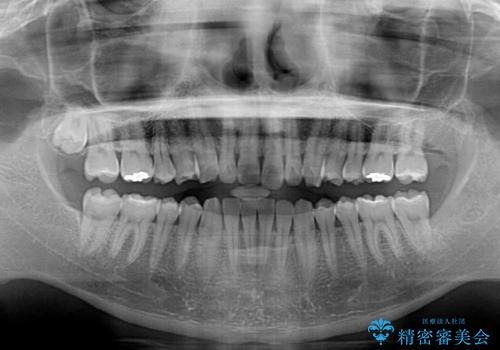

- 上下前歯のデコボコを気にして来院された患者様です。

以前矯正をした後戻りということで、歯列不正はそれほど大きくなかったため、インビザライン・ライトを用いて矯正治療を行うこととしました。